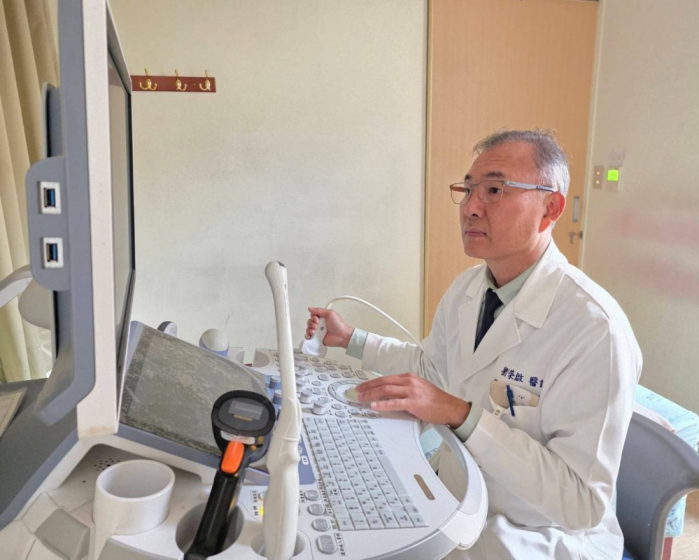

劉榮啟醫師提醒,婦科癌症初期徵兆往往不明顯,如出現持續性的腹脹、腹痛、食慾不振或異常陰道出血,女性朋友應提高警覺,切勿僅當成消化不良或經期失調。早期診斷、早期治療是提高存活率的不二法門,透過超音波檢查與癌症指數篩檢,多數婦科腫瘤都能被及時發現。他鼓勵女性應定期接受婦科檢查,即使面對癌症,現代醫學技術也能提供良好的預後與生活品質。